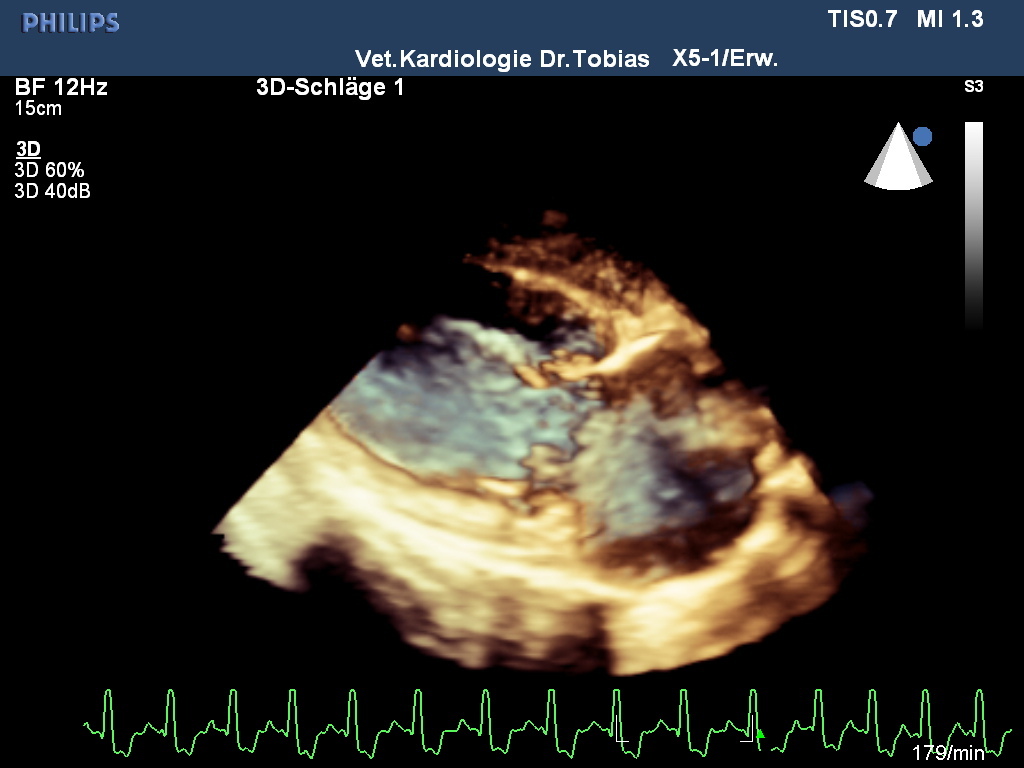

In der kardiologischen Diagnostik sind wir interessiert, diese Fälle so früh wie möglich zu ermitteln, um rechtzeitig ab gewissen Schweregraden therapeutisch sinnvoll gegensteuern zu können. Viele dieser Patienten gelten bei Hundebesitzern noch als asymptomatisch. Neben dem Vorbericht nutzen wir die klinische Untersuchung, das EKG, die bildgebende Diagnostik (radiologischen Thorax Untersuchung sowie eine standardisierte Echokardiographie mit ein- und zweidimensionalem Echo, sowie der Doppleruntersuchung). Spezialisten wenden auch 3D- und 4 D-Techniken an, die insbesondere bei Jetquantifizierung Vorteile haben. Zusätzlich werden Laboruntersuchungen genutzt, die kardiale Biomarker wie NTproBNP und sensitives Troponin I enthalten können.